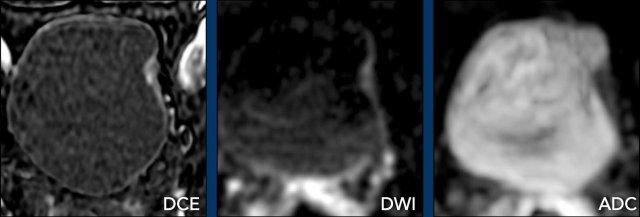

Dấu hiệu

- DCE: Ngấm thuốc sớm của lớp cơ được thấy rõ ràng trên chuỗi xung DCE.

Bản thân khối u nghèo mạch máu và không lan qua lớp cơ đang ngấm thuốc. - DWI/ADC: Có sự gián đoạn của cơ thành bàng quang, nhưng không có xâm lấn mỡ.

Kết luận

T2W 4/5, DCE 4 và DWI/ADC 4

Điểm VI-RADS cuối cùng: 4